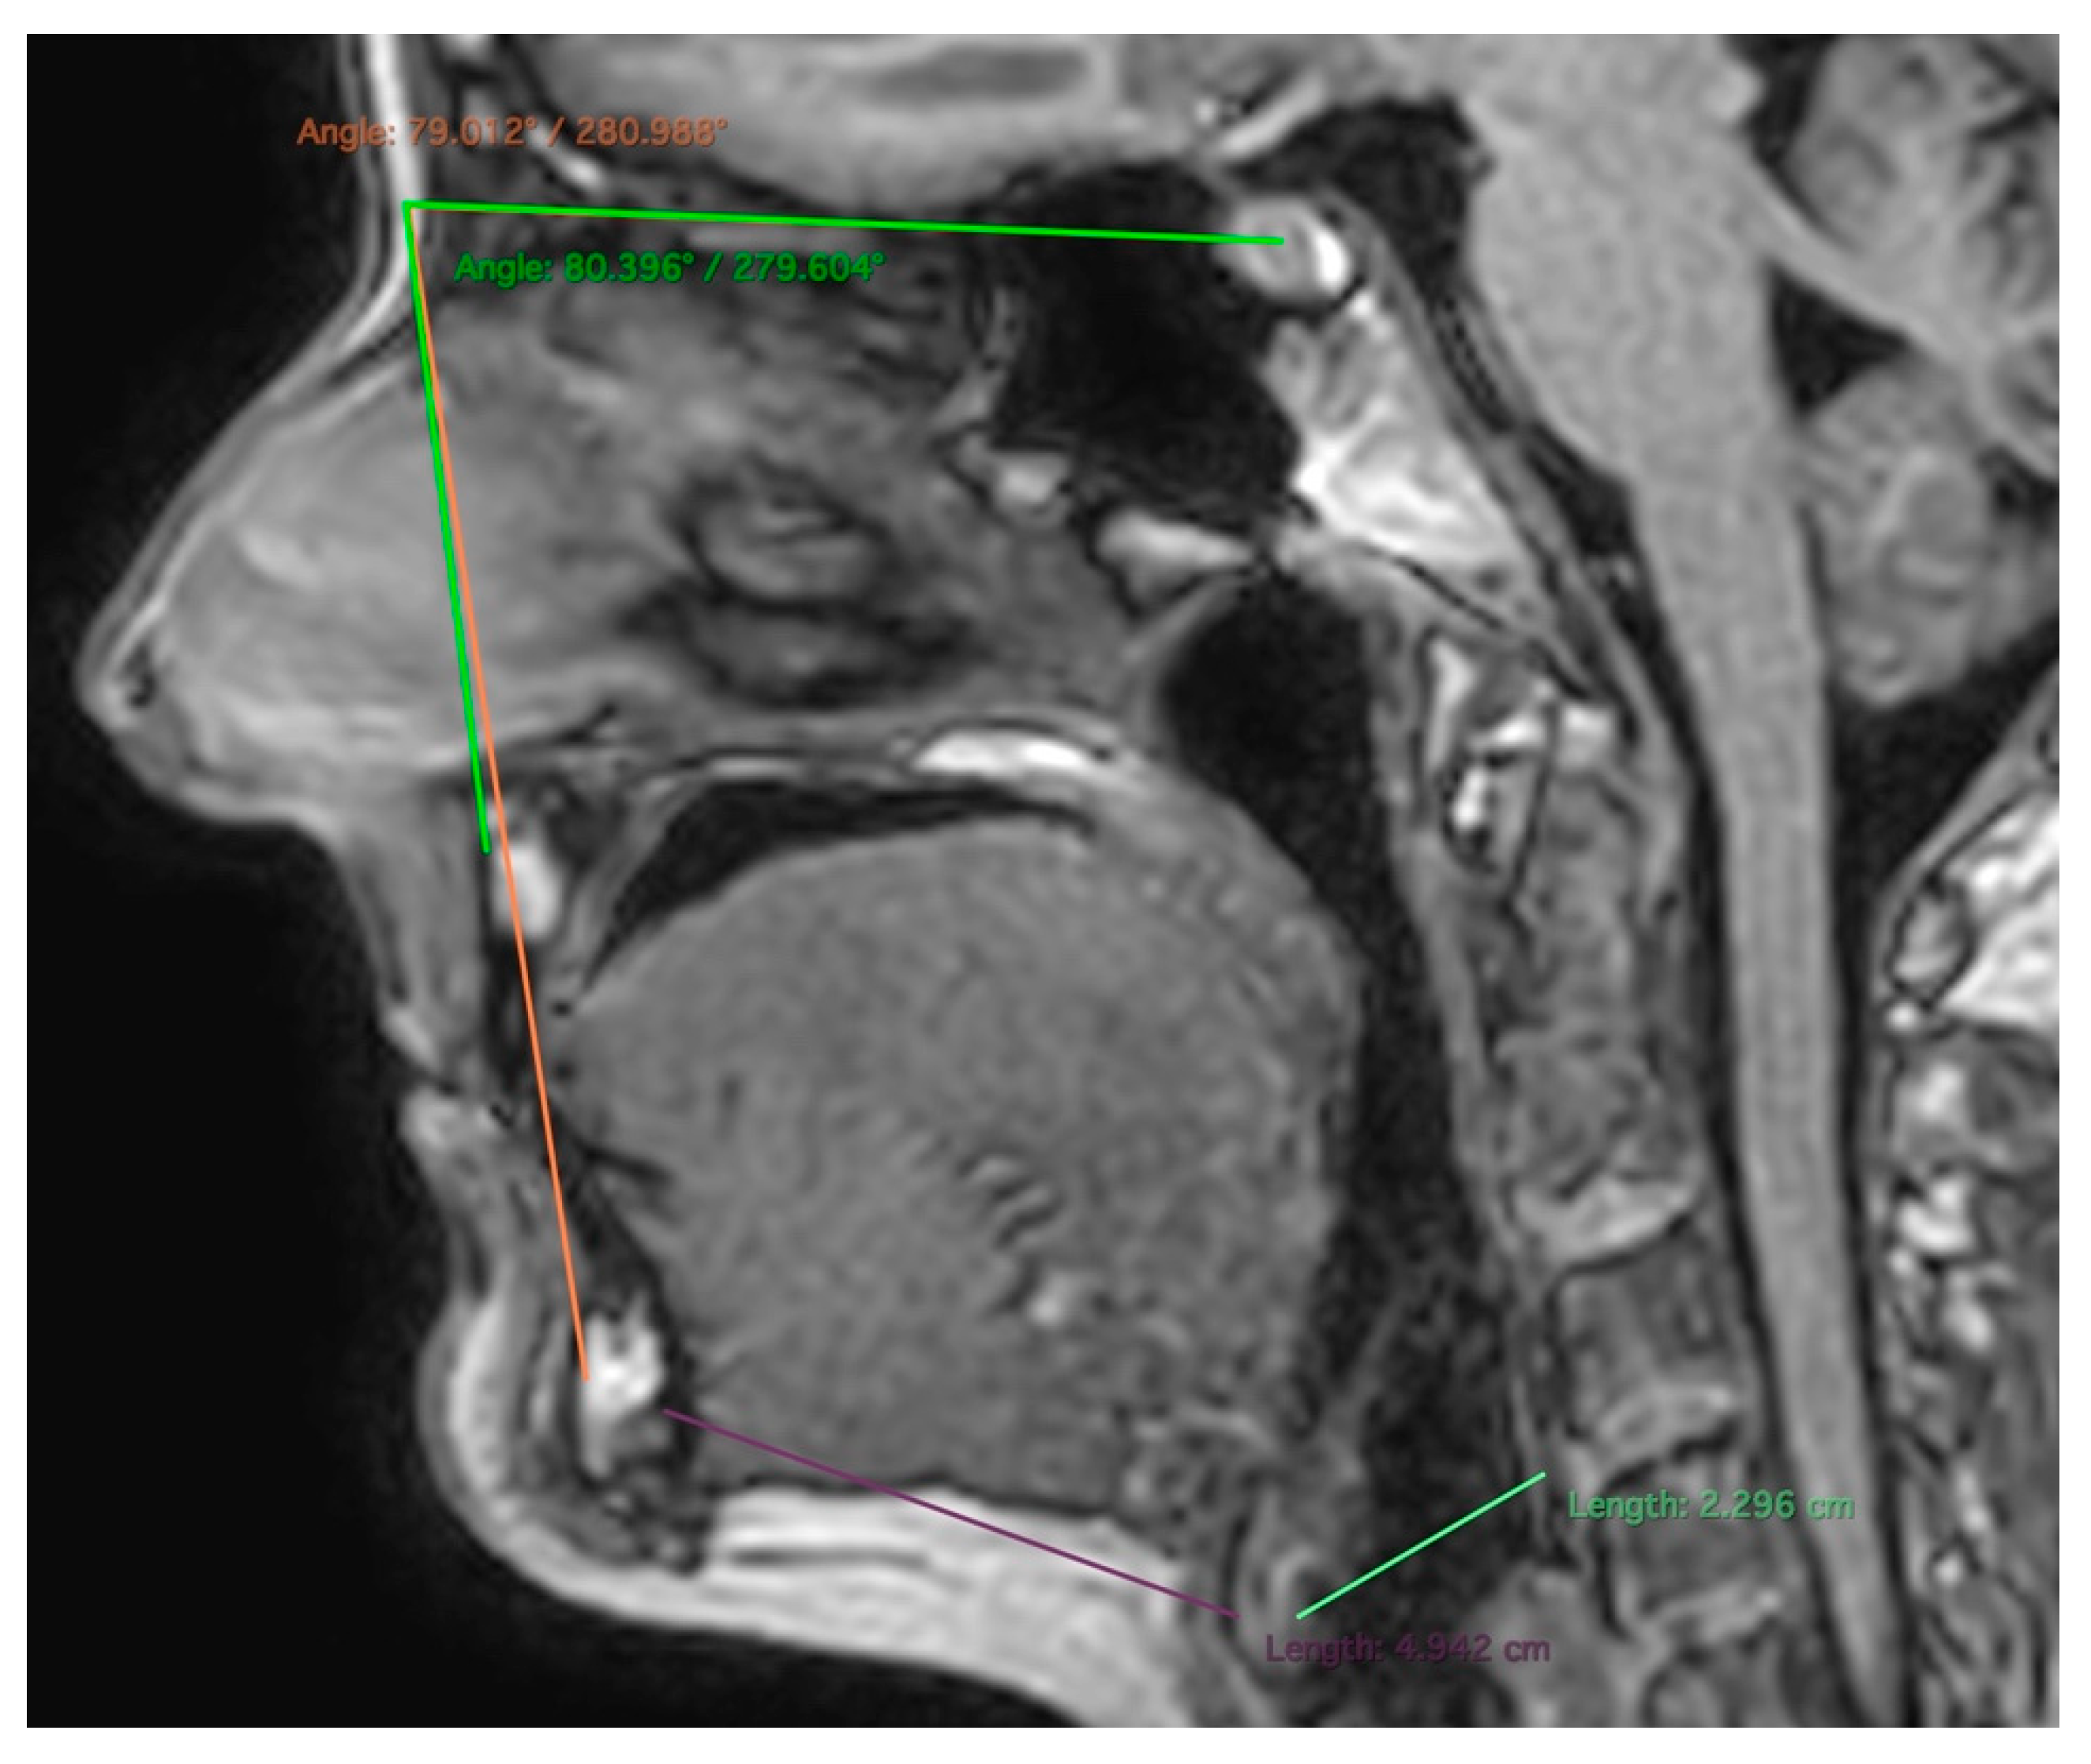

2.2. MR Imaging